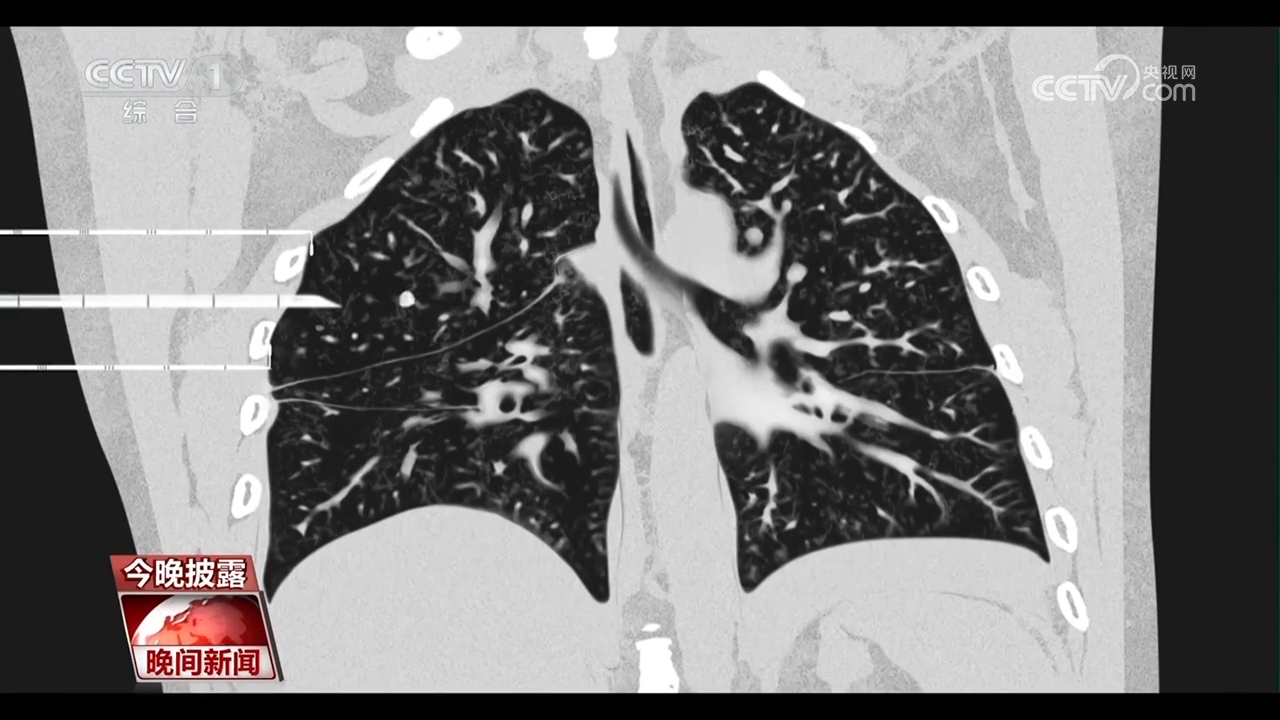

央视网消息:每年的11月是“全球肺癌关注月”。肺癌是我国发病率、死亡率最高的恶性肿瘤。随着胸部CT的普及,越来越多的肺结节被筛查出来。眼下正值年底体检高峰,一旦体检发现肺结节,就意味着会有发展成肺癌的风险吗?肺结节是否需要立刻手术呢?

专家介绍,2毫米以上的结节都能在CT上发现。肺结节不等于肺癌,而且绝大多数是良性的,胸部CT检查初次发现肺结节,先不要恐慌,应根据医生的建议定期复查,观察肺结节的变化。

首都医科大学宣武医院胸外科首席专家 支修益:特别是复合肺结节直径小于等于3厘米的磨玻璃结节,95%以上都是良性的,我们通过观察它的大小、边缘、密度的变化,来决定是否需要临床干预,而小于6毫米的,我们根本就不干预,年度健康体检就可以了。